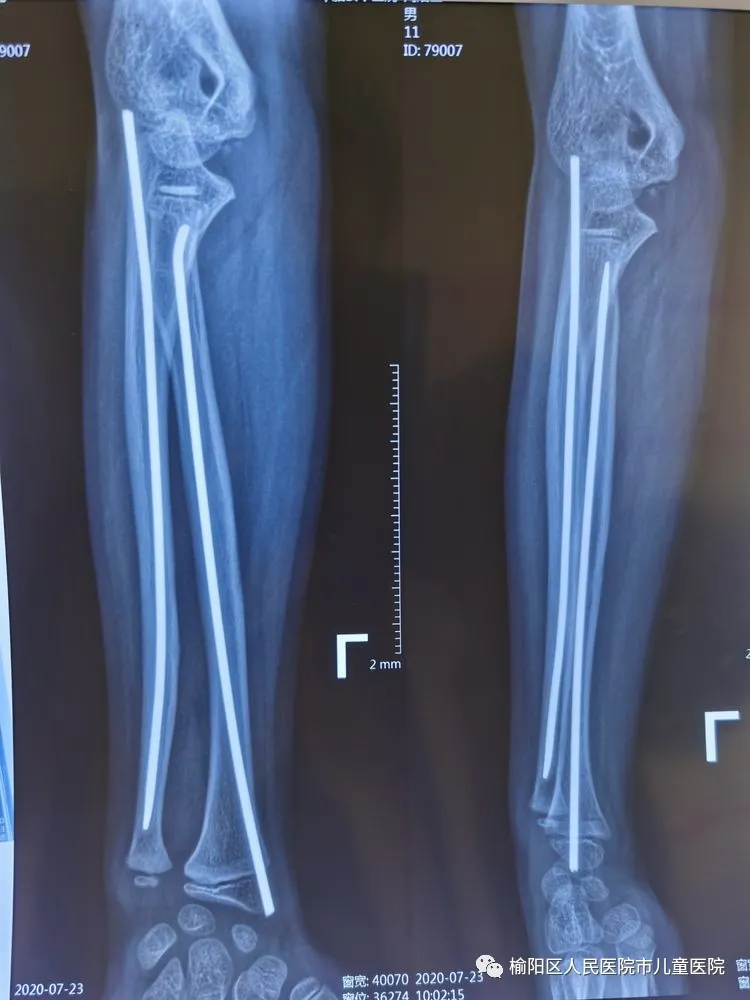

榆陽區(qū)人民醫(yī)院骨科——彈性髄內(nèi)針應(yīng)用分享

患兒12歲,因外傷致左尺橈骨骨折

復(fù)位外固定后家屬不滿意

在全麻下行彈性髄內(nèi)針微創(chuàng)閉合治療

0.5cm的微創(chuàng)小口

術(shù)后5個月,完美愈合。

彈性髄內(nèi)針治療小兒四肢骨折優(yōu)點:手術(shù)時間短,創(chuàng)傷小,住院時間短,骨折愈合快,費用低。